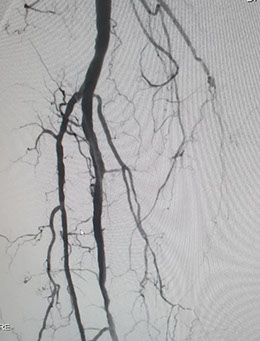

Las imágenes siguientes son previas al procedimiento y posterior se ve ambas arterias tíbiales permeables, y circulación en el pie